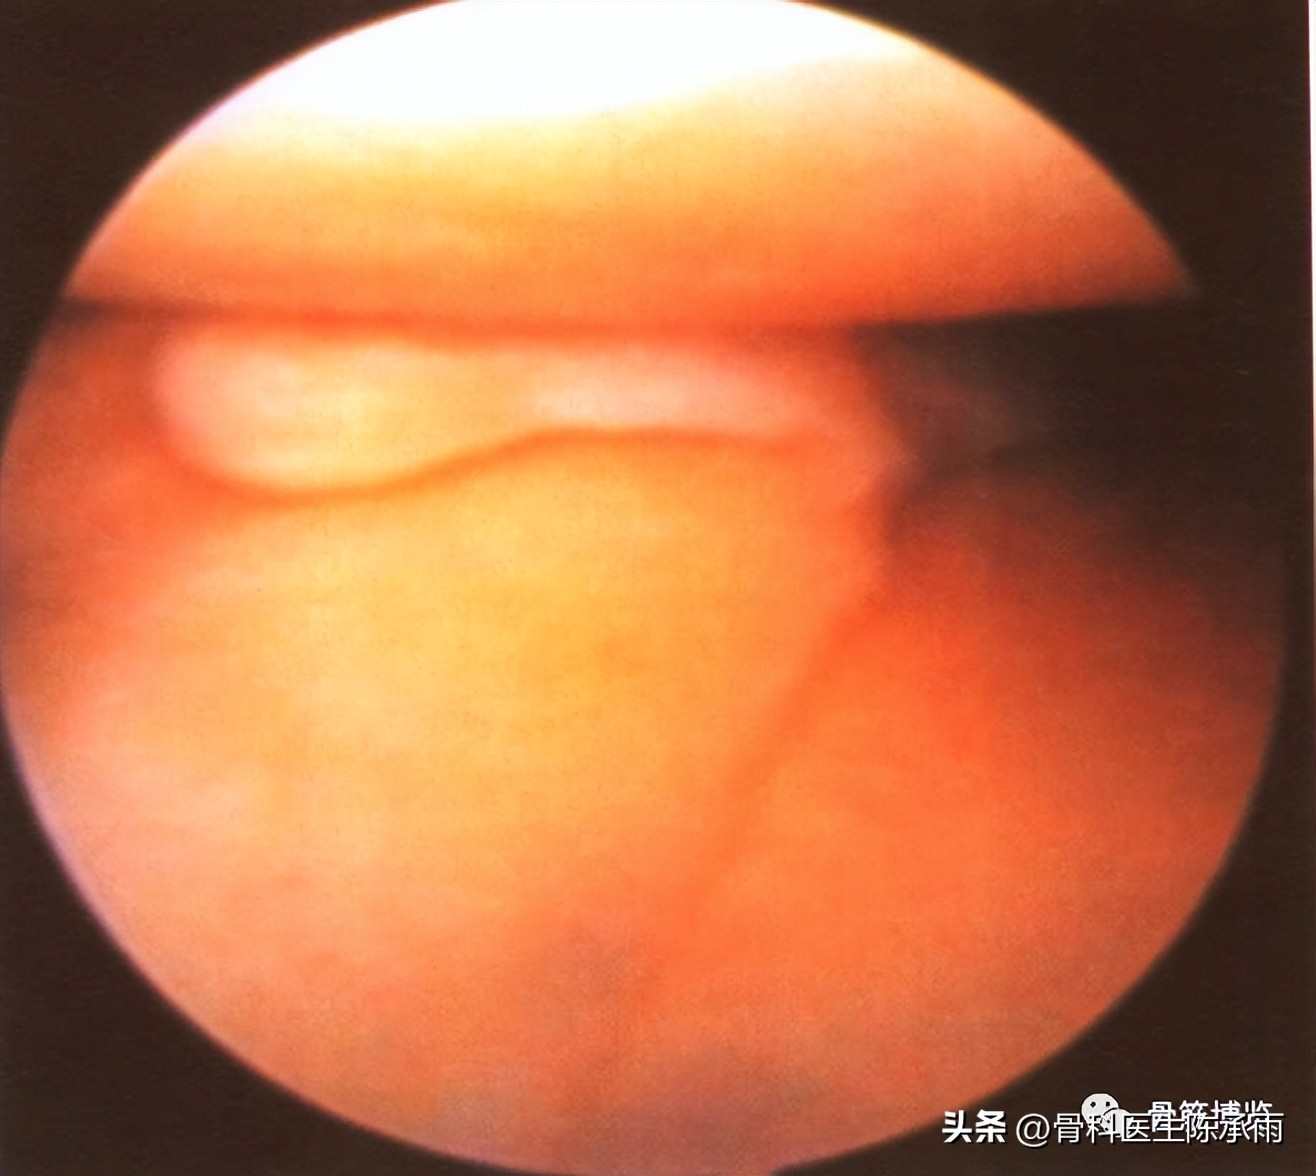

(一)纵裂

是指半月板的裂口与半月板纵轴相平行的撕裂。可以是垂直的,也可以是斜行的;可以是全层的,也可以是非全层的。常见于外伤直接的撞击或是随着关节囊的撕裂而形成。裂口为垂直方向的,与半月板边缘平行。其中又分为完全性的纵裂和不完全性的纵裂。完全性的(即全层的)纵裂,在裂口较大时,其内侧游离缘部分可以脱位于髁间窝,即形成典型的提篮状或者桶柄状撕裂。这种损伤容易导致关节绞锁,使关节屈伸受限。当撕裂时间较短,内侧的游离部分较完整,尚能较好地复位时,可以施行半月板缝合术,特别是接近滑膜缘的纵裂,缝合的效果较好,成功率较高。如果是不完全性的(即非全层的)纵裂则往往合并有层裂或斜裂,探查时应予注意。